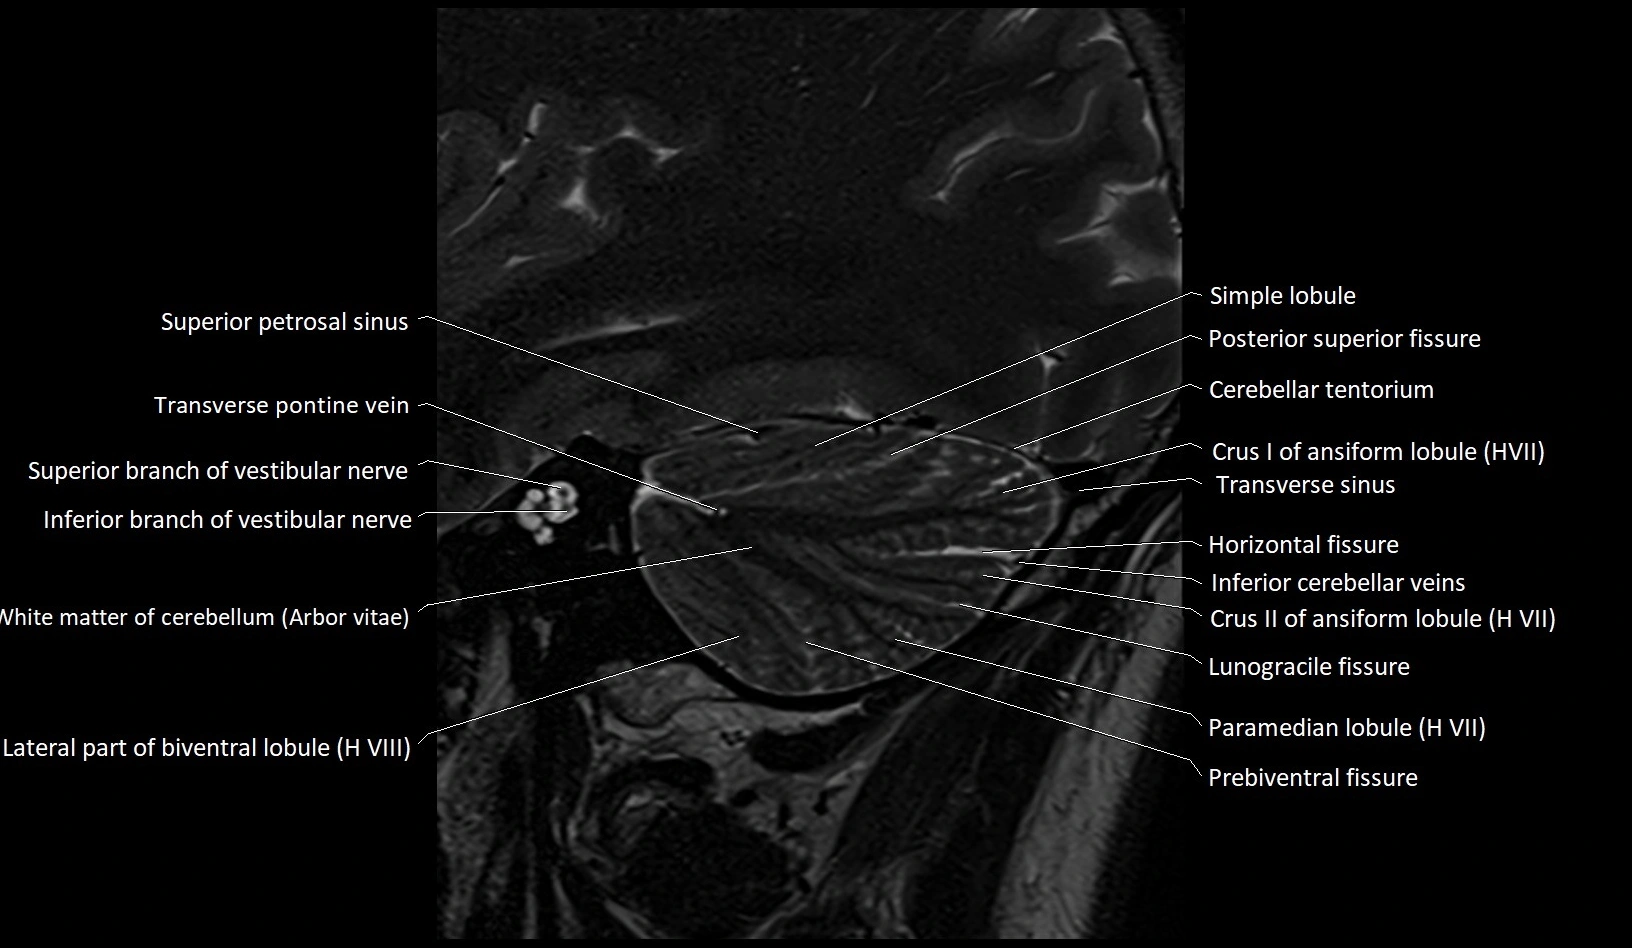

MRI images